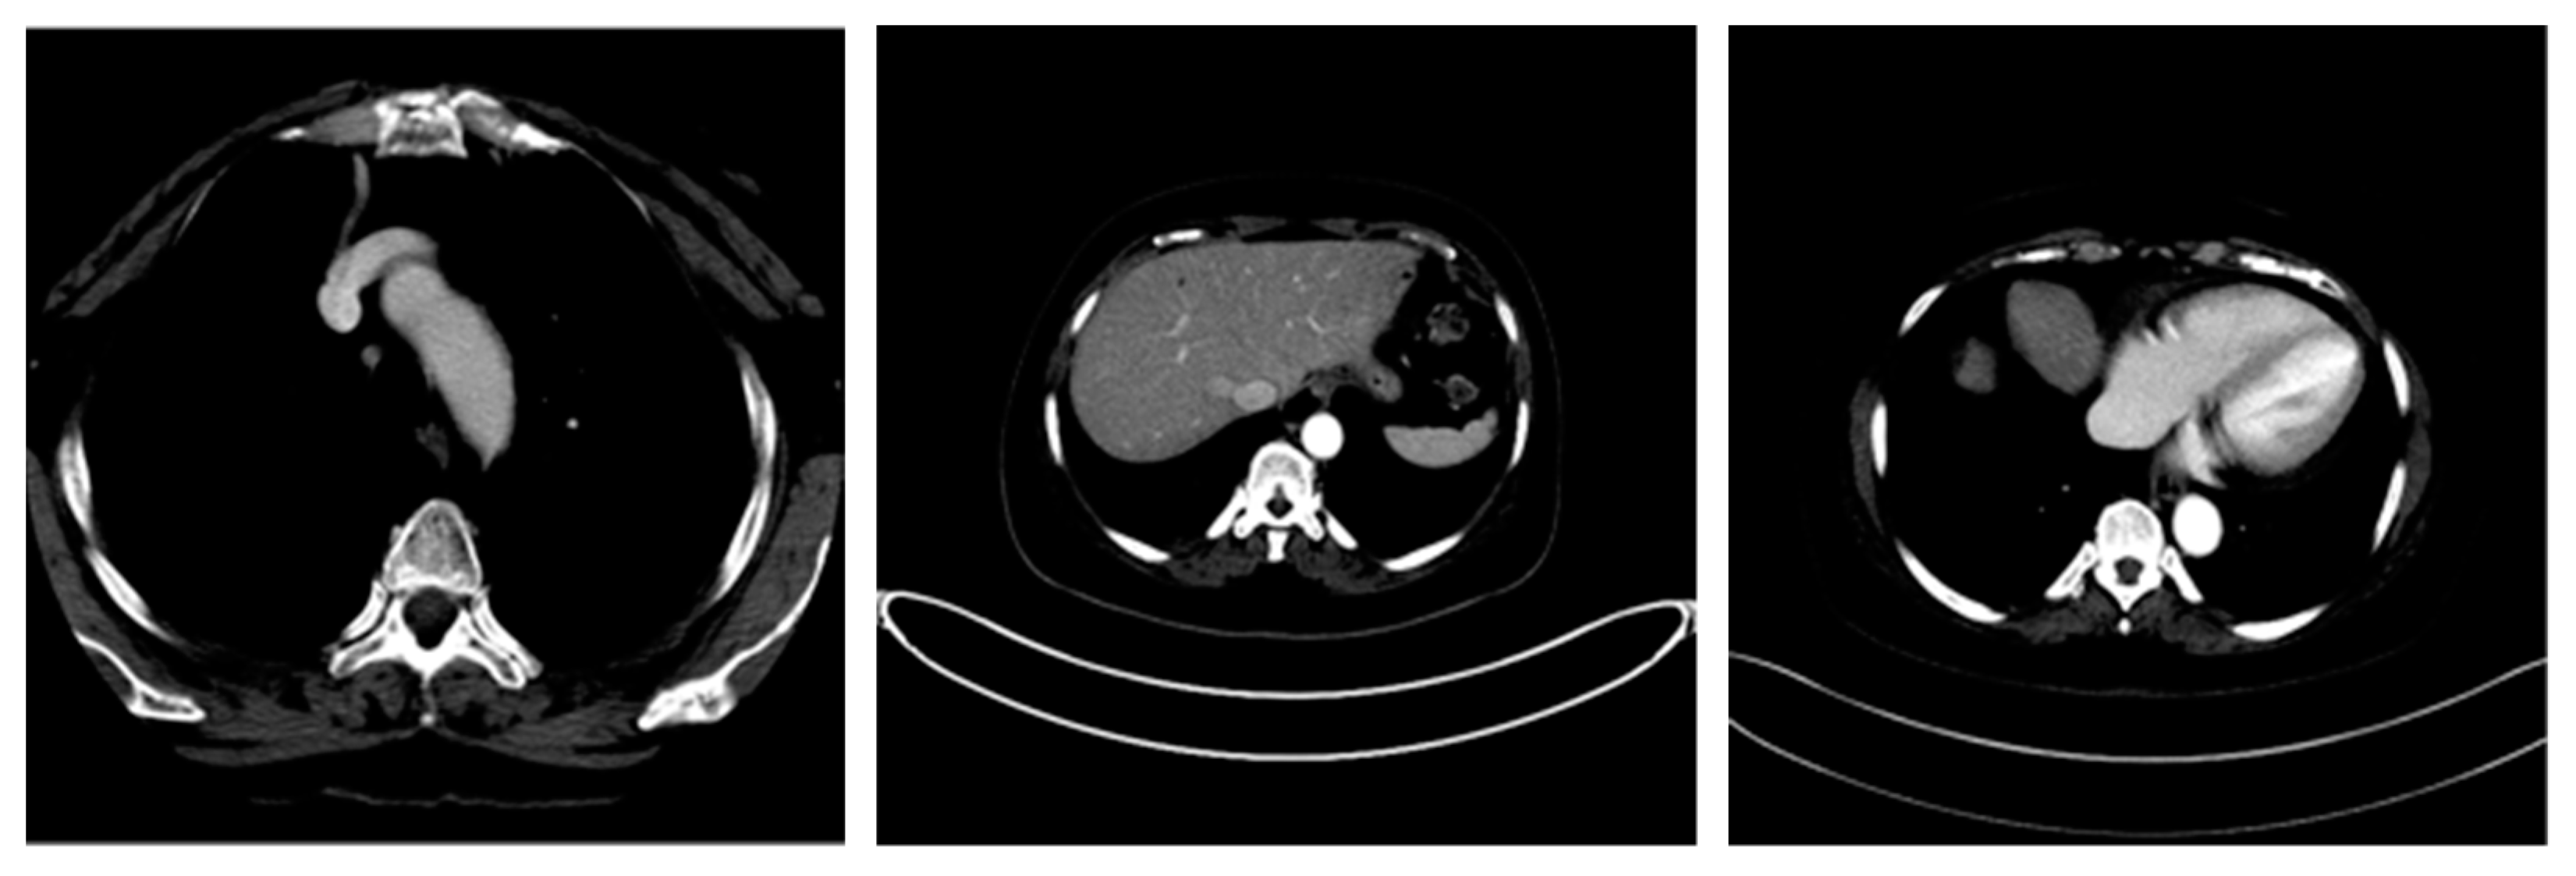

| Image Number | Overlaid Image | Deep Lesion Label | CNN Result | Clinical Radiologist’s Diagnosis | Grad-CAM Helpfulness |

|---|---|---|---|---|---|

| 7 | ![]() | Has Tumor | Has Tumor | Has Tumor | Yes |

| 8 | ![]() | Has Tumor | Has Tumor | Has Tumor | Yes |

| 9 | ![]() | Has Tumor | Has Tumor | Has Tumor | Some |

| 10 | ![]() | Has Tumor | Has Tumor | Has Tumor | Yes |

| 11 | ![]() | Has Tumor | Has Tumor | No Tumor (Cyst) | Some |

| 12 | ![]() | Has Tumor | Has Tumor | Has Tumor | Yes |

| 13 | ![]() | Has Tumor | Has Tumor | No Tumor | Yes |

| 14 | ![]() | Has Tumor | Has Tumor | No Tumor (Inflammation of the Biliary Tract) | Some |

| 15 | ![]() | No Tumor | Has Tumor | No Tumor (Cyst) | Some |

| 16 | ![]() | Has Tumor | Has Tumor | Has Tumor | Yes |